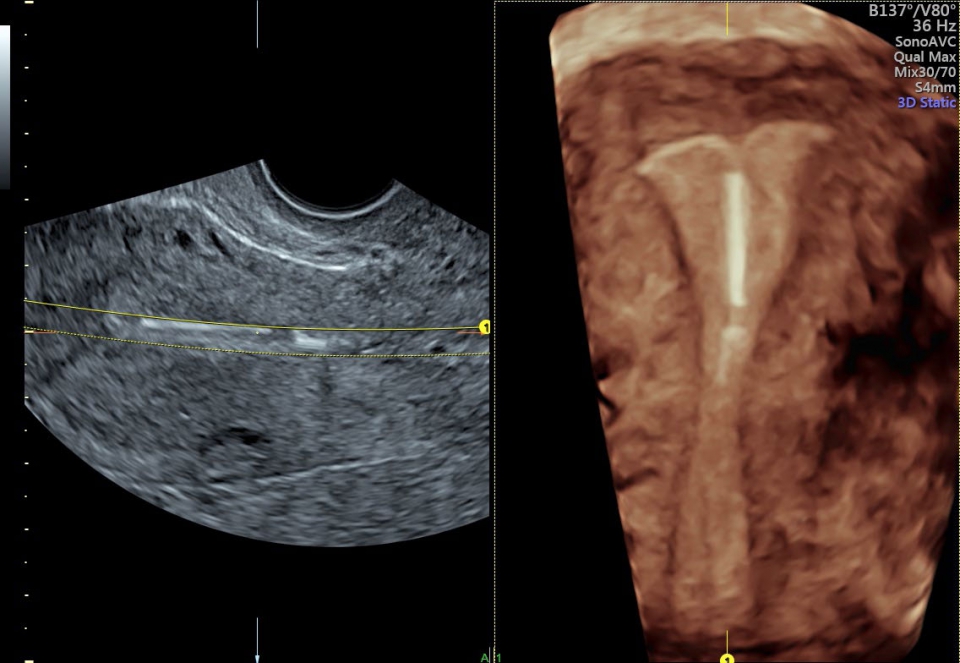

• SonoAVC (Автоматический расчет объема): Эта функция позволяет визуализировать и рассчитывать размеры и объем гипоэхогенных образований, таких как фолликулы яичника или структуры головного мозга плода. Она помогает в оценке этих образований и отслеживании их изменений в течение времени.

SonoAVC:

Да

• SonoAVC (SonoAVC follicle, SonoAVCantral).SonoVCAD labor - программное обеспечение для исследования во втором периоде родов